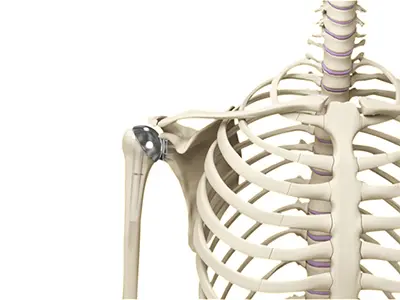

Shoulder Joint Replacement

Total shoulder replacement surgery is performed to relieve symptoms of severe shoulder pain and disability due to arthritis.